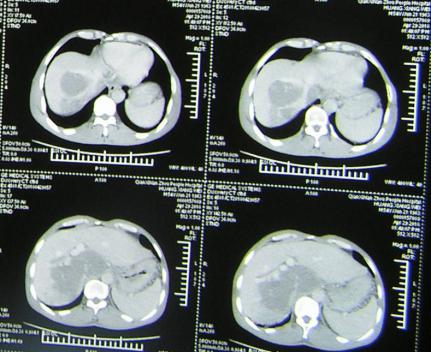

如解剖性精准肝叶、肝段切除,胰十二指肠切除,全胰腺切除,肝门部胆管癌根治(围肝门切除),胆管损伤修复,门脉高压断流、分流等。以下是部分手术图片。

一、肝切除

1. 肝门区域阻断超右半肝切除